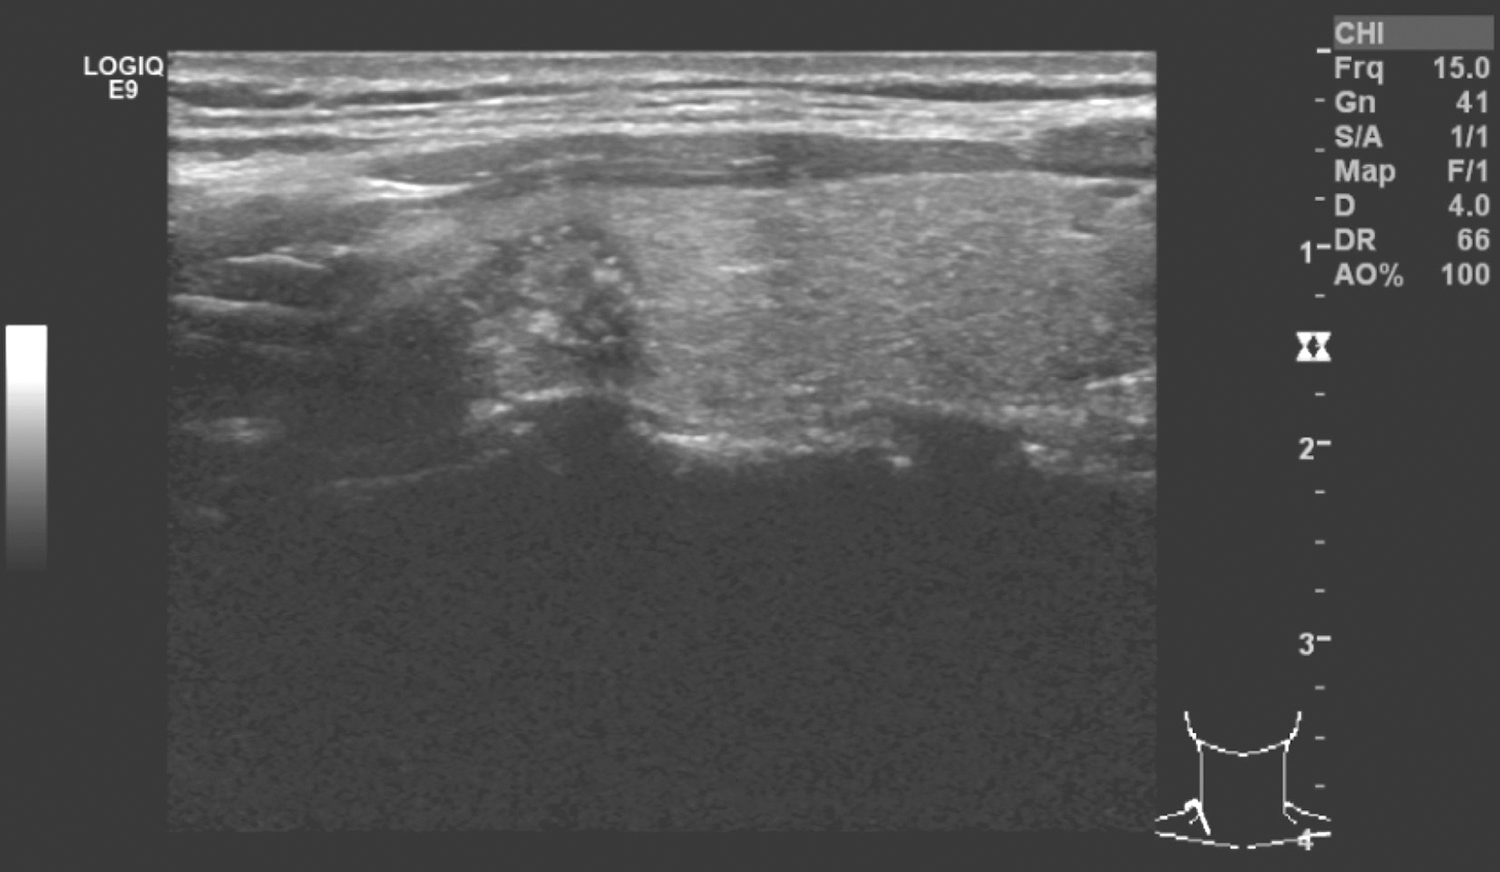

1小时条评论42岁男性,因发现甲状腺肿物1个月余入院。术前结合病史和辅助检查,确诊为甲状腺癌右颈淋巴结转移,如何处理? (一)病例简介 患者男性,42岁。因发现甲状腺肿物1个月余于2017年2月22日收住院。1个月前患者体检发现甲状腺肿物,无声嘶、吞咽不适、呛咳、憋...